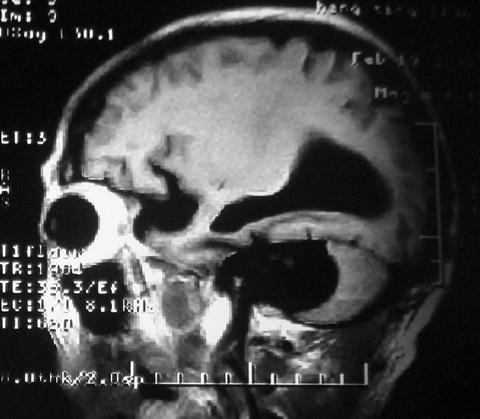

m,72,头疼,头晕两年,伴视力模糊三月,饮食呛咳两天。pe:颈部抵抗,左眼突出,左眼瞳孔约3mm,对光反射消失,双眼失明,伸舌困难,双肺呼吸音粗,心率110次/分,左上肢肌力i级,左下肢屈曲,肌张力高。现有08年2月19mri平扫及10年2月8日mri增强请会诊。ct病灶呈低密度伴散在点、片状等密度区,无明确钙化(无ct片资料可供上传)。[

脑外肿瘤,囊实性,环状不规则强化,内听道扩大,考虑神经源性肿瘤

左侧桥小脑区占位伴梗阻性脑积水----考虑 1神经鞘瘤 2室管膜瘤。

脑外肿瘤,病灶呈匍匐蔓延,表皮样囊肿可能性大。